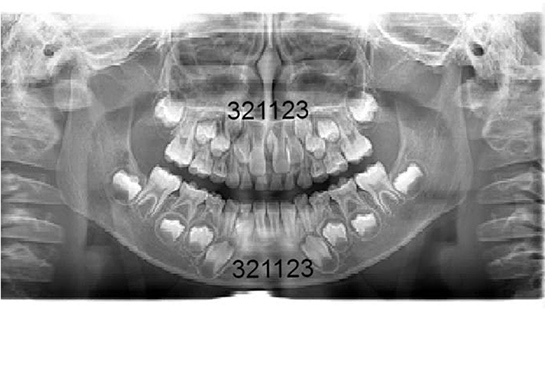

術前と術中のレントゲン写真

• 術前のレントゲン写真

上顎の3番目の犬歯のスペースがほとんどありません。 下顎も同じように3番目の犬歯のスペースが僅かですが不足しているのが解ります。 このままですと特に上顎の前歯は凸凹になり、犬歯は間違いなく八重歯になるでしょう。

• 術中のレントゲン写真

上顎の左右の2番目から2番目の4歯は綺麗にはえることができ、3番目の犬歯のスペースができました。 下顎も同じように3番目の犬歯のスペースができました。これで八重歯になる事はなく自然に萌出することを待ちます。